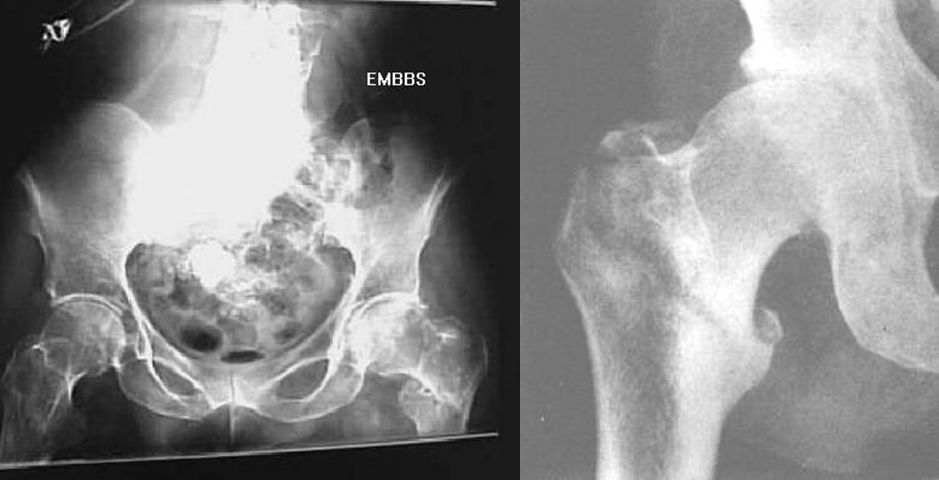

髋关节后脱位

髋关节前脱位

先天性髋脱位

常见髋关节测定线